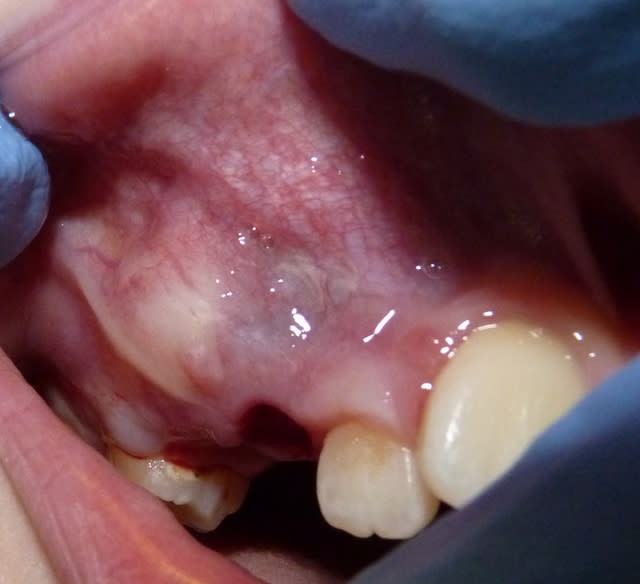

DOULET_I_20111201_1010_xieidx.jpg

Voir le message contenant cette image